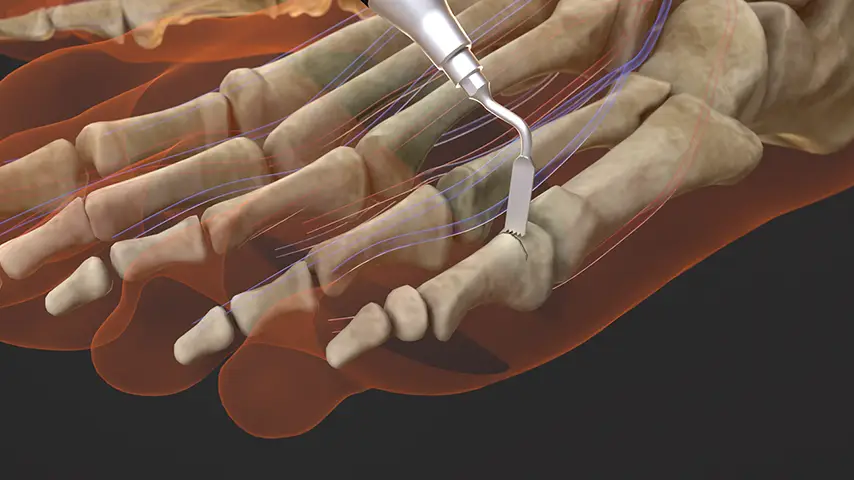

Forefoot Deformity Correction

Details

Multiple metatarsal osteotomies benefit from the technology’s selective cutting, which enables precise bone reshaping in narrow spaces. This enhances the restoration of forefoot alignment with reduced collateral tissue damage.

Recommended insert: